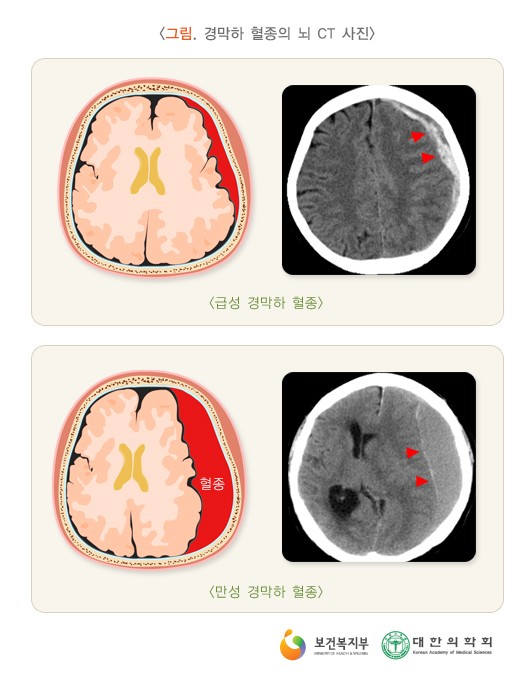

만성 경막하 출혈 원인, 증상, 치료, 예후와 합병증 정리

만성 경막하 출혈은 뇌와 척수를 둘러싸고 있는 경막하 공간에 혈액이 지속적으로 누출되는 질환을 말합니다. 경막하 공간은 뇌와 척수를 보호하는 역할을 하고, 이 공간에 혈액이 누출되게 되면 뇌와 척수에 압력이 가해져 다양한 증상이 나타납니다. 1. 만성 경막하 출혈의 유병율 유병율은 정확하게 알려져 있지 않지만 인구 10만 명당 약 1~2명 정도로 발생한다고 합니다. 모든 연령대에서 발생할 수 있으나 50~60대 성인에게 가장 흔합니다. 2. 원인 1) 외상 : 머리 부상이나 축추 부상이 만성 경막하 출혈의 가장 흔한 원인입니다. 2) 혈관 질환 : 뇌동맥류, 뇌혈관 기형, 척추동맥류 등이 원인이 될 수 있습니다. 3) 혈액 질환 : 혈우병, 혈소판 감소증 등이 만성 경막하 출혈을 유발합니다. 4) 수술 ..